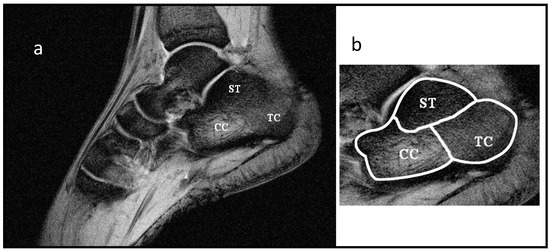

We also performed a FLASH T2*–T1-weighted image at 3.0 T using square FOV = 180 mm, matrix = 512 × 512, TE = 10 ms, TR = 600 ms, and BW = 160 Hz/pixel as a reference to discriminate the calcaneus zones ST, TC, CC characterized by different trabecular bone density. In Figure 1, an example of this acquisition is reported with the selected subtalar (ST), tuber calcanei (TC), and cavum calcanei (CC).

ROIs. In all the MRI sequences, no chemical pre-saturation pulses were used for either fat or water protons.

As reported in the Introduction, T2* and T2 measurements of spongy bone are indicated in the literature as promising parameters to develop an NMR approach to diagnose osteoporosis. To test the potentiality of this method in detecting variation in trabecular bone density, as occurs in osteoporosis, we focused our attention on three different calcaneal sites characterized by different trabecular bone density: the subtalar (ST), the tuber calcanei (TC) and the cavum calcanei (CC) as represented in Figure 1. The ST region is characterized by the highest trabecular density. Trabecular density progressively decreases when moving from TC to CC regions. The CC region is characterized by the lowest and isotropic trabecular density [43]. To evaluate SNR, the most common TE values used in radiological imaging of spongy bone were chosen for FLASH and MCSE images. At 1.5 T and 3.0 T, the SNR was measured from FLASH and MCSE images at TE = 5 ms and 45 ms, respectively, as the ratio of the mean signal, measured in each of the three regions of interest (ROI), and the mean value of the background noise (measured in a region of no signal). For consistency, ROIs were placed at an identical position on each image by the same operator (shown in Figure 1b), selecting the slice of the center of the calcaneus.

Figure 1. (a) T2*–T1-weighted image obtained at 3.0 T. (b) Selection of ROIs that correspond to the three calcaneus areas of interest: ST, subtalar region, TC, tuber calcanei region, CC, cavum calcanei region. Image resolution was 0.35 × 0.35 × 5 mm3.